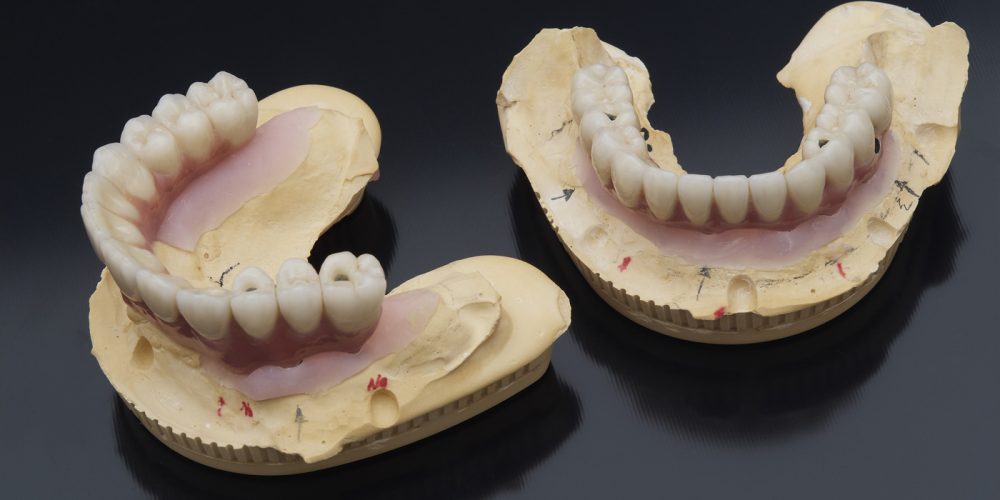

L’impianto dentale è una vite in lega di titanio che sostituisce la radice naturale del dente mancante. Agli impianti inseriti nelle ossa mascellari è applicato un perno moncone (detto abutment) che sostiene la corona avvitata o cementata. In questo modo viene ricreato totalmente il dente, dalla struttura interna alla corona esterna.

PROTESI COMPLETA SU IMPIANTI

In molti casi il paziente tollera con difficoltà la classica dentiera che appoggia esclusivamente sulle gengive soprattutto per la difficoltà di ottenere una buona stabilità della protesi. In alcuni casi si può ottenere la risoluzione del problema andando ad inserire 4 impianti sui quali verrà avvitata una protesi fissa (protesi All On Four) che potrà essere confezionata ed adattata nelle 24 ore successive all’intervento di implantologia. Grazie all’utilizzo delle diagnosi con TAC Cone Beam e al confezionamento di dime chirurgiche l’intervento risulterà molto rapido e dal dolore post operatorio molto contenuto.